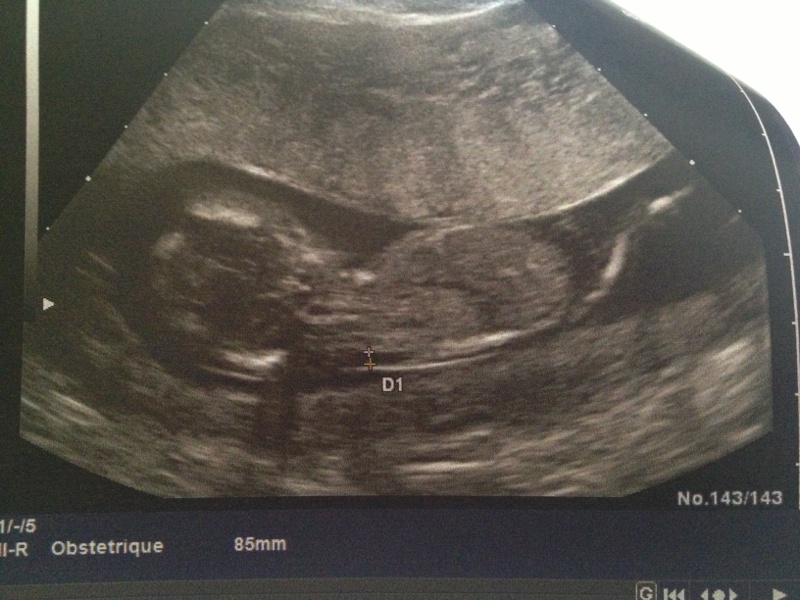

louloute26 a dit:Coucou les minettes!! Cette aprem a 15h15 je vais faire mon echo!!! J'espère que tout ce passe bien et j'espere que je pourrai découvrir le sexe!! Hihihi j'suis pressé!!!!